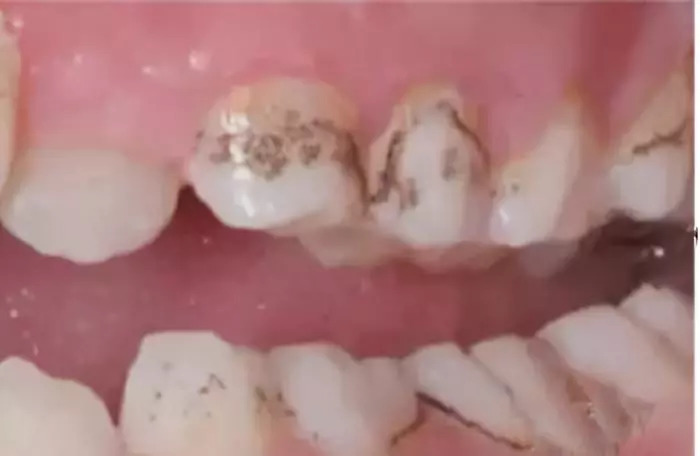

2. 牙齿●发黑↓↓

分为三种即:牙面色素沉着、牙齿受伤、龋齿(也就是蛀牙)

龋齿(也就是蛀牙):宝宝牙齿发黑是否是龋齿,有个简便的判断方法:妈妈可以用牙签划在黑点处,如果滑动自如,表明牙面光滑,可能就不是龋齿了;如果牙面坑坑洼洼,牙签不能自如划过,这多半就是龋齿了,最好找牙医确诊。